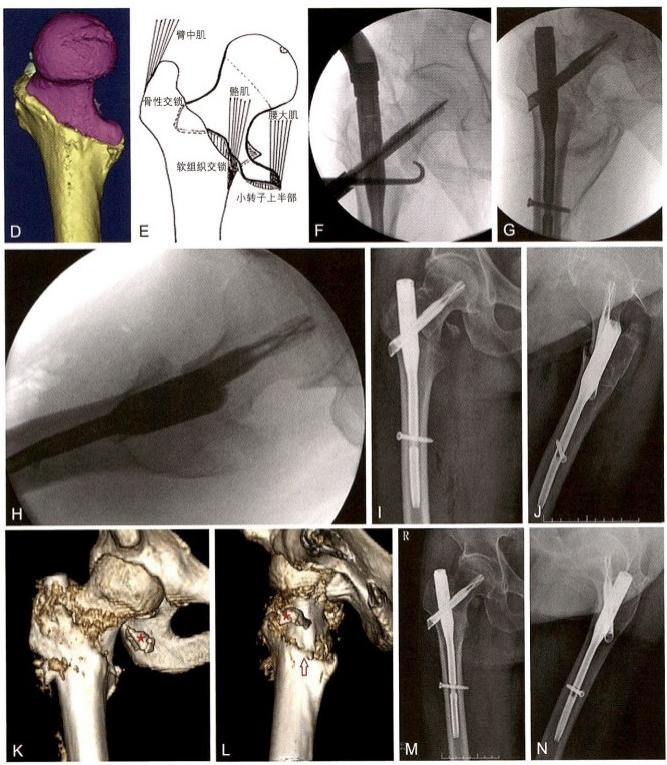

患者男,56岁,因助动车车祸发生左侧股骨转子间骨折。入院后经 术前检查,诊断为全转子区骨折,属于极不稳定类型。第三天在骨科牵 引床上进行头髓钉内固定手术。

通过手法操作,获得了头颈骨块与股骨干的良好对线。从螺旋刀片打入的切口,通过微创钢丝导入器在小转子骨块导入钢丝,准备在头髓钉插入后进行捆扎。按常规方法插入短型InterTan髓内钉,将其内芯 锁定螺钉拧紧,防止头颈骨块进一步滑动。在股骨干处将远侧交锁螺钉 打入在动态位。术毕捆扎钢丝时,发现仅前内侧骨皮质(占环周皮质的 1/6~1/4)有确实可靠的接触抵住,其余部分均呈缺损状态。收紧小转子 钢丝,将其直接捆扎在髓内钉主杆上,只能放弃,将其拆除。

术毕透视,骨折复位质量优(4分),内固定稳定性优(7分)。术后 三维CT 证实仅前内下角获得骨皮质对骨皮质的可靠支撑。术后卧床2个 月,拍片发现前内侧角皮质愈合后开始扶双拐下地,1个月后扶单拐行 走。随访7个月,骨皮质愈合范围达到1/3周径,外侧壁也出现骨桥连接。 患者已去拐自由行走,功能良好(图9-22)。

图9-22 全转子区骨折。A.术前X线片,显示为31 A3型骨折;B 、C.术前三维CT示 骨折为全转子区骨折,分别有头颈骨块、股骨干骨块、小转子骨块、外侧壁骨块,前 壁骨块大转子分裂为前后2块;D~F. 采用mimics软件模拟骨折复位,显示骨折粉碎 程度

图9-22 ( 续 )G 、H. 闭合复位获得良好对线之后,微创导入钢丝,准备捆扎收拢小转 子骨块;I. 头髓钉手术之后,收紧小转子钢丝,但捆扎在髓内钉主杆上。为了避免干 扰骨折愈合,将其拆除;J 、K 、L. 术毕透视正位、侧位和前内侧斜位,示内芯螺钉拧 紧,远侧交锁螺钉打入在动力位;M 、N. 术后第5天拍片,示环周骨皮质缺损很多;O 、P. 术后三维 CT 显示仅前内下角约1/6的环周皮质相互抵住

图9-22 ( 续 )Q 、R.三维CT透明处理显示头髓钉内固定位置良好,髓内钉充满髓腔, 消除了髓内钉的摆动(雨刷效应);S 、T. 术后7个月,透视示股骨颈无短缩,内侧股 骨距愈合良好,外侧壁也出现骨桥连接。注意:与术后即刻相比,交锁螺钉上移